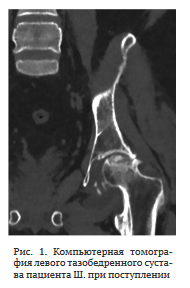

Пациент поступил в клинику НМИЦ ФПИ с жалобами на боль и резкое ограничение движений в правом тазобедренном суставе. Функциональные показатели сустава по шкале HHS — 25, по шкале WOMAC — 84, выраженность болевого синдрома по шкале ВАШ — 6 баллов.

На рентгенограмме правого тазобедренного сустава визуализировали контактную деструкцию суставных концов, сужение суставной щели (рис. 4).

Под лучевым контролем выполнена трепанационная биопсия головки правой бедренной кости.

Исследование биологического материала: ДНК МБТ не обнаружена. При определении РНК вируса иммунодефицита человека методом ПЦР-РВ (HIV) в биоптате обнаружено 6,7*104 коп/мл. Микроскопия операционного материала: отрицательно. Микробиологическое исследование операционного материала: роста микроорганизмов не выявлено. Гистологическое исследование: признаки неспецифического коксита. Иммунологическое исследование крови: СД4 — 19 % — 654 кл/мкл, РНК ВИЧ — 120 коп/мл. Учитывая данные анамнеза и гистологического исследования, установлен диагноз: правосторонний неспецифический коксит.

07.03.23 произведена операция в объеме резекции головки бедренной кости, установки артикулирующего спейсера из костного цемента с клиндамицином (4,5 г) (рис. 5). Выбор клиндомицина обусловлен близким к линкомицину механизмом действия и антимикробным спектром (в анамнестических данных пациента есть указания на положительный эффект применения линкомицина), а также высокой элюционной способностью препарата [25].